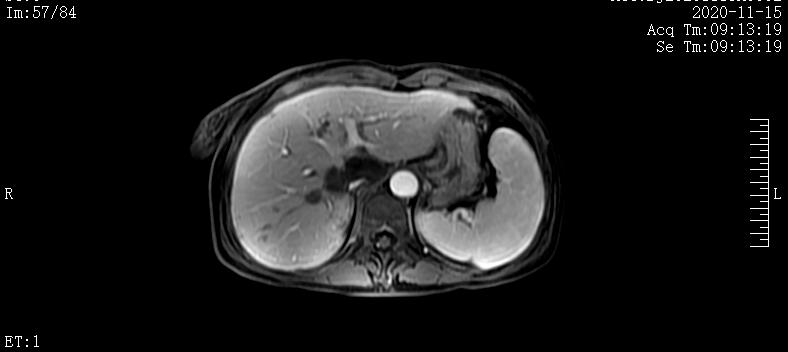

2020-4-20肝脏MRI提示:肝内多发团块,肝门及腹膜后淋巴结肿大;胰腺体尾部团块

2020-6-17肝脏MRI提示:1.胰腺体尾部异常信号,较前略缩小。2.肝内多发结节及团块,考虑转移瘤,部分病灶较前缩小。3.腰1-3椎体异常信号强化范围较前略缩小

2020-8-22肝脏MRI提示:1.肝脏多发异常信号,较前稍缩小。2.腰椎内异常信号,较前缩小

2020-11-15